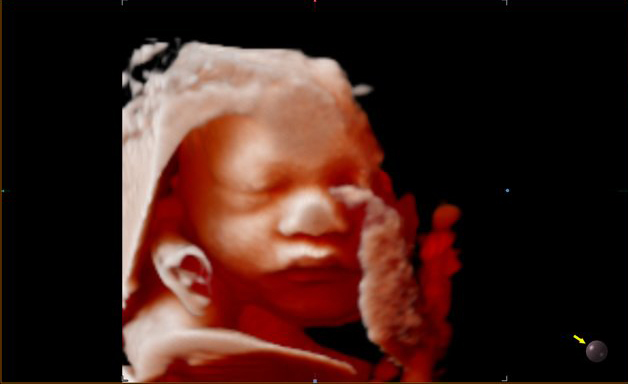

Siêu âm 5D không phải là siêu âm năm chiều. Một số phòng khám khẳng định siêu âm 5D mang lại chất lượng tốt nhất. Nhưng trên thực tế, nó chỉ có ưu điểm hơn trong việc tái hiện “đẹp” hơn hình ảnh em bé dưới nguồn sáng ảo do tích hợp công nghệ phủ màu giúp hình ảnh về em bé chân thực hơn. Về kỹ thuật siêu âm, nó không khác biệt so với siêu âm 4D.

Bên cạnh đó, công nghệ siêu âm 5D có thể hỗ trợ tốt hơn cho bác sĩ trong việc rút ngắn thời gian thực hiện các phép đo và tăng độ chính xác kết quả do tính chất tự động quét và hiển thị các thông số.

Tuy nhiên, không phải lúc nào đây cũng là ưu điểm bởi vì kinh nghiệm và tay nghề kỹ thuật viên mới là điều kiện tiên quyết cho ra kết quả siêu âm chính xác nhất, đặc biệt là trong những trường hợp xuất hiện bất thường hay đôi khi máy móc không nhận dạng được do sự thay đổi vị trí nằm của thai nhi…

sieu-am-5d Hình ảnh siêu âm 5D